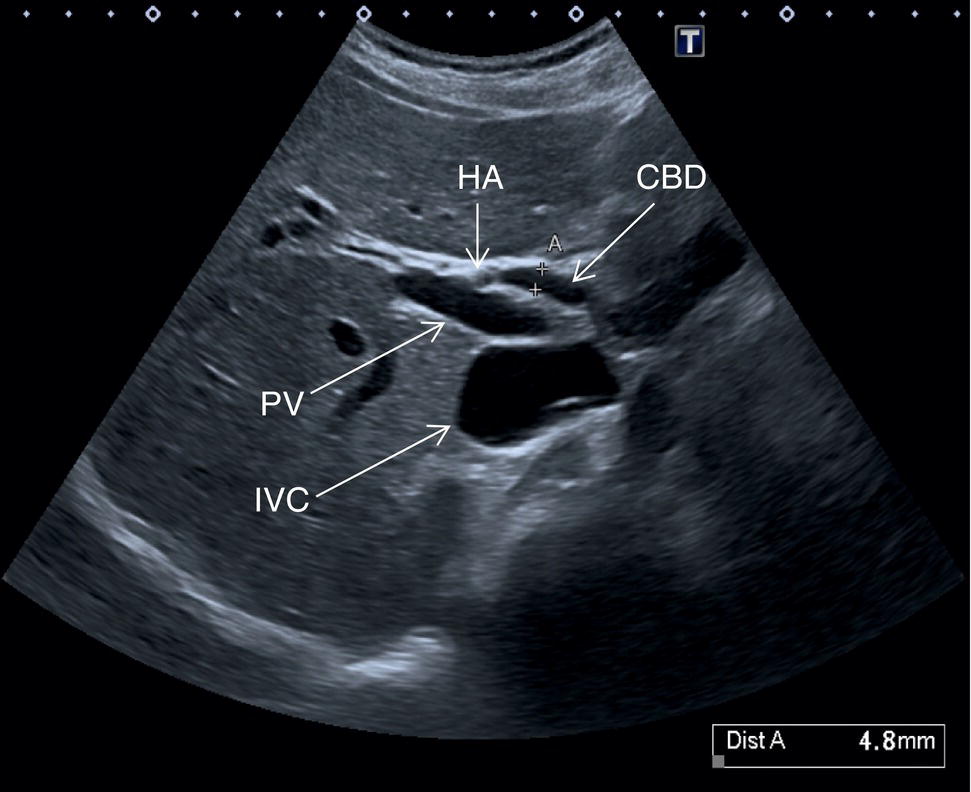

The GB is assessed in the subcostal position, in two orthogonal planes, and also intercostally. As a first approach, place the transducer on the anterior abdominal wall along the mid‐clavicular line, adjusting its position until the GB is located. Ask the patient to take a deep breath to lower the diaphragm and push the liver downwards below the costal margin; this will facilitate GB visualisation. It is essential to image the GB in its entire long axis and to angle the transducer so that it is also imaged transversally. The longitudinal intercostal approach will complete the GB visualisation, also offering an alternative to a sometimes challenging subcostal view in case of bowel gas interposition (Figure 3.27) (Video 3.9). In other circumstances, especially in the presence of narrow intercostal spaces, an intercostal approach might not be ideal. The CBD is best visualised with the patient supine or slightly turned with the left side down. Start with the probe obliquely positioned in the epigastrium, in line with the anatomical plane of the CBD. Sweep subcostally and outwards until you see the image of the portal triad (Figure 3.28). This may require some fine adjustments of the probe position (Video 3.10). The CBD is usually measured longitudinally where the HA intersects the CBD and PV; nevertheless, if the CBD shows some size variations it should be measured at the level of its maximal calibre (Figure 3.29). As for the GB, there may be occasions, owing to bowel gas, in which the CBD is better visualised in the anterior intercostal plane (Figure 3.30). ![]()

The PV calibre is measured at the hepatic hilum at the crossing with the HA, where a diameter up to 12.5–13 mm is considered normal (Figure 3.34).

The HA has echogenic walls, it runs anteriorly to the PV and posteriorly to the CBD, and its normal calibre at the hepatic hilum measures up to 3 mm in diameter (Figure 3.34). The hepatic veins have thinner and less echogenic walls [8] and have a straighter and linear course compared to the portal venous system. Although the measurement of the hepatic veins is usually not performed on a routine basis, the cut‐off value of their calibre is approximately 8 mm, measured at about 2–3 cm from their confluence into the IVC [9]. It should be kept in mind that in lean subjects both IVC and hepatic veins may be more ectatic. When performing a liver ultrasound scan it is important to keep in mind that the echogenicity of both hepatic veins and PV walls changes according to the angle between the ultrasound beam and the vascular wall. The more acute is the angle of insonation, the closer it is to being parallel to the longitudinal axis of the vessel. Therefore, despite there being clear differences between the thick perivascular collagen of the portal venous system and the thin walls of the hepatic veins (Figure 3.35), if the angle of insonation is low between the ultrasound beam and the PV walls, these could appear very thin or even not be visible. On the other hand, if the angle of insonation with the hepatic veins is close to 90°, the walls will appear thick and echogenic. It is always important to keep in mind this physical principle, remembering the anatomical landmarks and tracing the vessels to their origin: the PV to the hepatic hilum and the hepatic veins to their confluence into the IVC.

In normal physiological conditions, the CBD is the only biliary duct that can be clearly seen as a thin tubular structure with echogenic walls that in the majority of cases runs anteriorly and parallel to the PV at the level of the hepatic hilum (Figure 3.8). However, the anatomical relationship of the biliary ducts and the portal vessels may vary along their course, and usually the peripheral biliary ducts (which are only clearly visible when dilated or significantly thickened) run posteriorly to the PV (Figures 3.9 and 3.10).

The CBD measures between a minimum of 2–3 mm and an upper limit of 6–7 mm. Larger calibres are observed, especially post cholecystectomy and with age, where it is generally accepted that the calibre may increase by 1 mm each decade after 70 years [3].